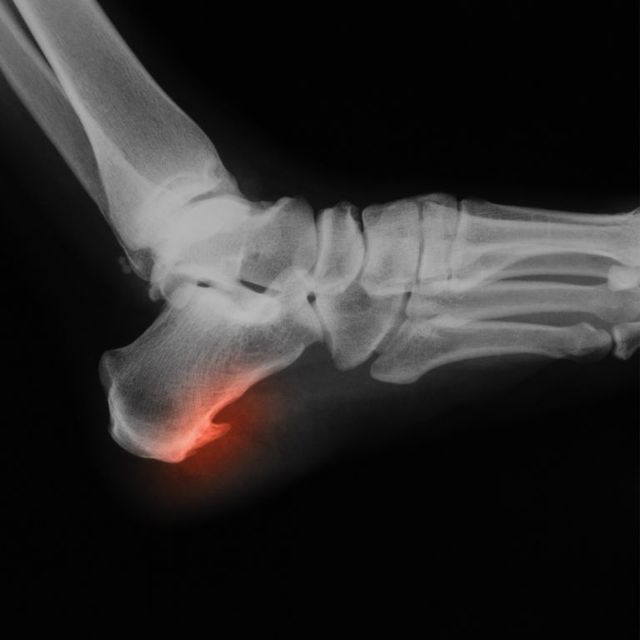

Esporão calcâneo

Protuberância óssea no calcanhar associada a inflamação dos tecidos.

Causas

Arco do pé elevado ou muito rígido, impacto repetido.

Tratamento

Palmilhas, adaptação do calçado, fisioterapia. Casos graves podem exigir infiltrações ou cirurgia.

Prevenção

Bom amortecimento, calçado adequado e gestão de carga.

Pode-se correr com isto?

Depende da dor e da inflamação.